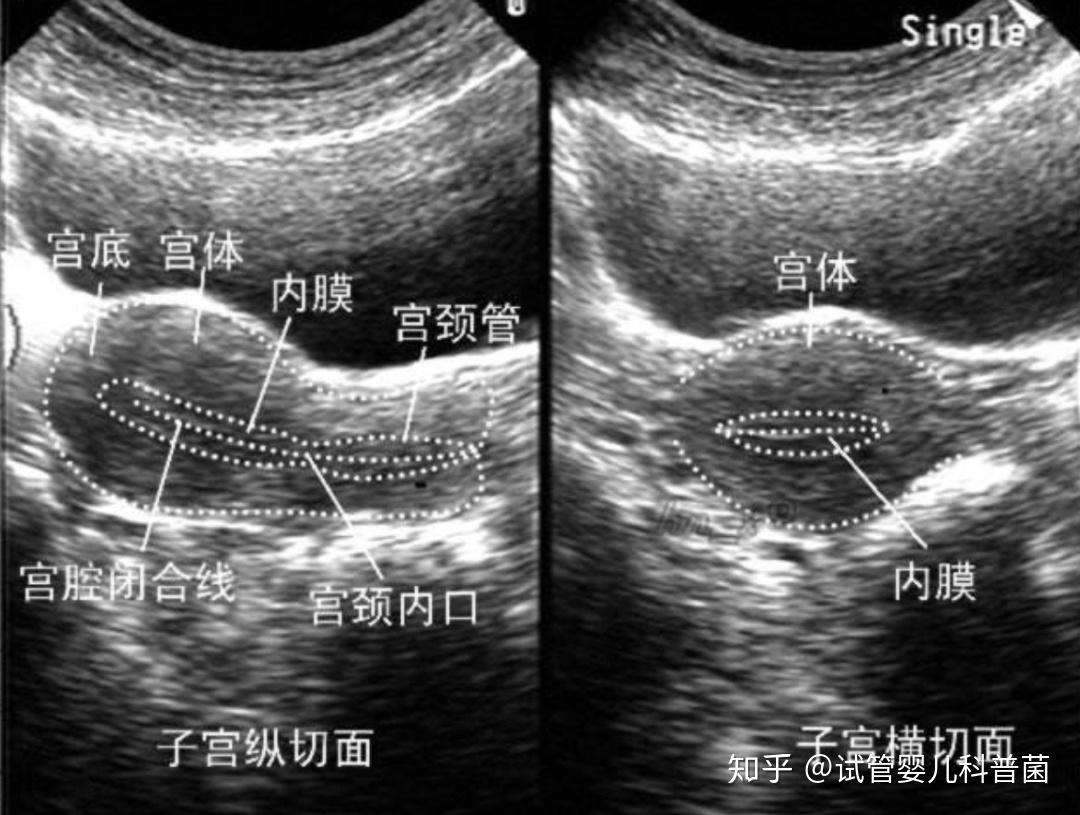

子宫内膜正常是多少mm(什么是子宫内膜过薄)